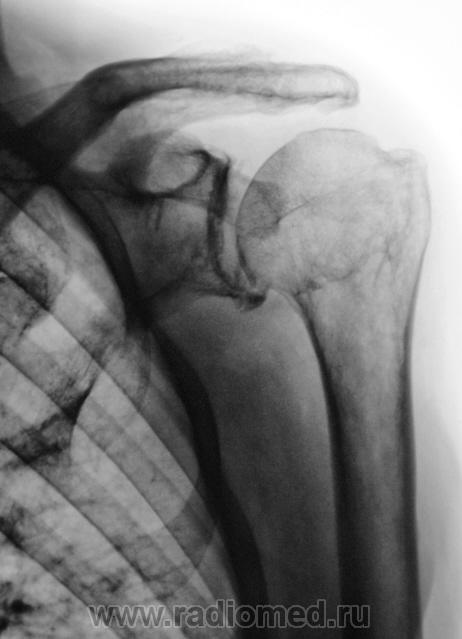

На следующий день пациент был осмотрен хирургом, и был направлен на рентгенографию другого плечевого сустава.

В правом - последствия травмы (подвывих, перелом головки?)

Травму пациент не помнит...

Двусторонний деформирующий остеоартроз: справа усилен верхним подвывихом с образованием неартроза с акромиальным отростком.

2-сторонний ДОА, справа подвывих, неоартроз + калькулезный (известковый) бурсит(возможно тоже 2-сторонний)